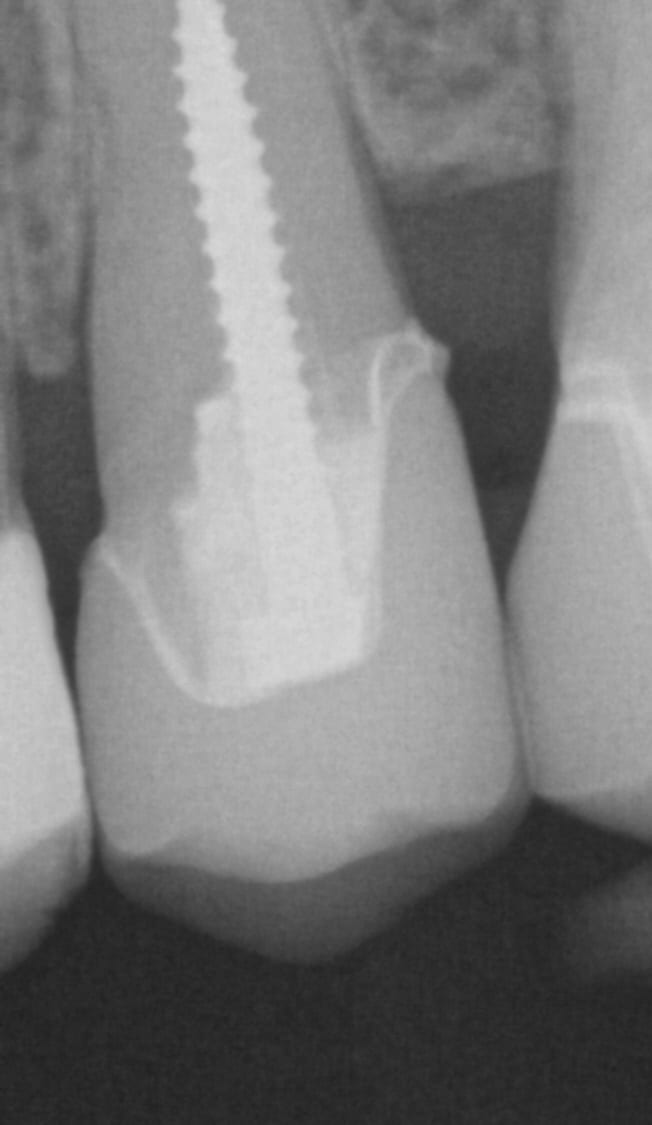

IMMEDIATE POST OP X-RAYS